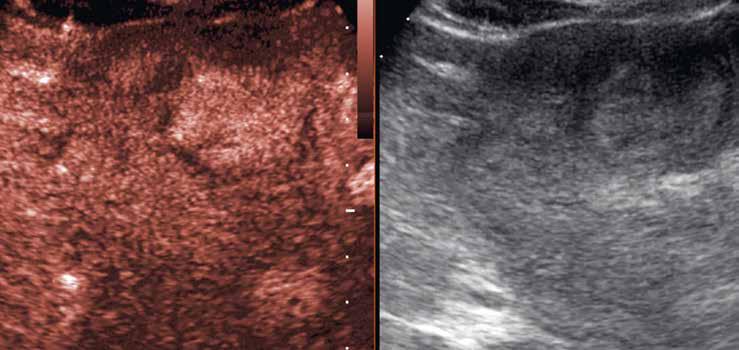

Po aplikaci kontrastní látky se ložisko v arteriální fázi homogenně sytí (96–100 %) (obr. 6–10). Sycení je typicky intenzivní, ale na krátkou dobu, a ve 40 % případů –i když v některých publikacích se popisuje až u 90 % případů – může být patrný jeho loukoťovitý charakter („spoke-wheel pattern“) (obr. 6–8). Ten je zřejmý u větších

Na CEUS je v arteriální fázi patrný v levé polovině obrázku typický centrifugální charakter sycení ložiska, které je vidět v pravé polovině obrázku v B -módu (jako hypoechogenní) (6–8). Na CT (9) i MR (10) se ložisko (z obr. 4, 5) sytí homogenně, vyjma centrální vazivové jizvy, která zůstává hypodenzní.